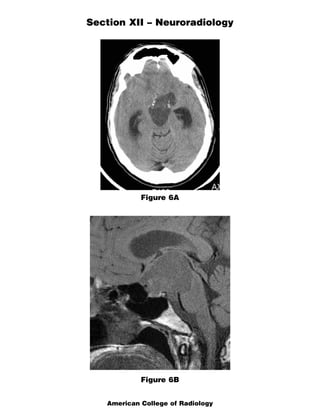

The document discusses several radiology cases involving the brain and spine. Question 291 presents CT scans of a woman with headaches and asks for the most likely diagnosis of a fat-containing extraconal orbital mass. Question 292 shows MR images of a woman with extremity weakness and asks for the most likely diagnosis of multiple brain and spine lesions. Question 293 presents MR images of a man with back pain and asks for the diagnosis of a posterior spinal mass seen on the images.